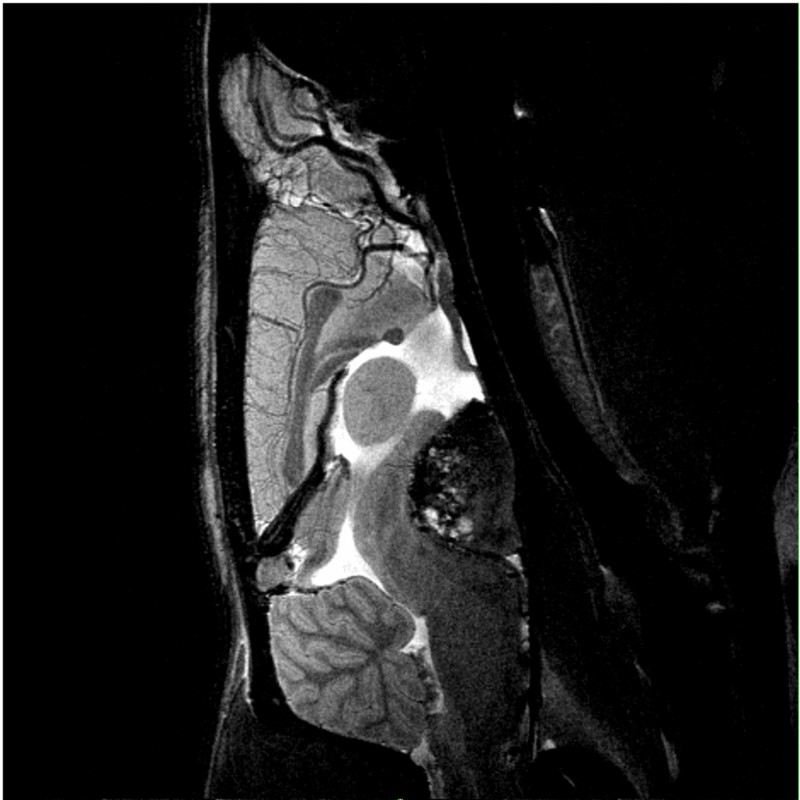

• Unique Ultra Shielded technology, requiring no cold head, for greatest physical stability imperative in motion-sensitive studies, such as fMRI

• Over 100 validated and ready to use in vivo protocols and scan programs for mice and rats

• MRI sequence portfolio of more than 1,000 sequence variations, including wireless cardiac imaging using navigator based IntraGate methods with cartesian or radial readout, as well as short echo time imaging, such as UTE and ZTE